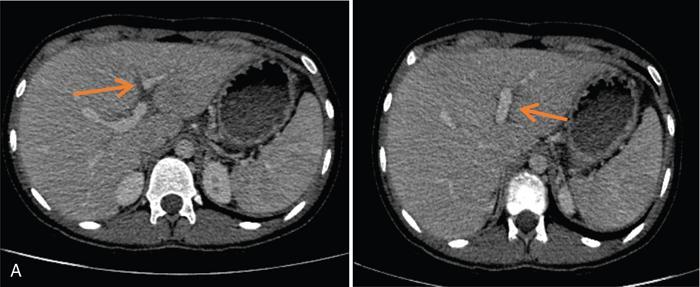

Excessive triglyceride accumulation within hepatocytes is defined as hepatic steatosis. Major conditions associated with hepatic steatosis include alcoholic fatty liver disease (AFLD) and nonalcoholic fatty liver disease (NAFLD). Causes of hepatic steatosis are discussed in Table 9.10.3. NAFLD is the most common form of hepatic steatosis and discussed in detail below. Up to 90% of patients with chronic alcoholic intake have fatty liver. Those with pure AFLD have a 10% risk of progressing to cirrhosis. Consumption of 30 g ethanol/day shows increased risk of chronic liver disease and cirrhosis. Other risk factors include female sex, obesity, cigarette smoking, obesity and associated risk factors. These factors are divided into 2 main categories which can cause fatty liver: inborn errors of metabolism and acquired metabolic disorders. Inborn errors of metabolism include abetalipoproteinemia, galactosemia, glycogen storage disease, hereditary fructose intolerance, homocystinuria and Wilson disease. Inflammatory bowel disease, jejunoileal bypass, malnutrition, starvation and total parenteral nutrition are acquired metabolic factors associated with increased risk. Chronic HCV infection, is associated with hepatic steatosis, with prevalence of 40%–80%. Hepatic steatosis can be seen as an adverse reaction to some medications such as tetracycline, valproic acid, some of chemotherapeutic agents, dexamethasone, amiodarone, methotrexate, tamoxifen and acetylsalicylic acid. Either microvesicular or macrovesicular steatosis can be observed in drug-induced hepatic steatosis. It generally occurs with therapy lasting several weeks or months and is reversible after discontinuation. The leading cause of hepatic steatosis in paediatric population is NAFLD. Six per cent of these patients develop cirrhosis and end-stage disease. Other less common causes include starvation and malnutrition, drugs (glucocorticoids, oestrogens, tetracyclines, and methotrexate), intoxications (carbon tetrachloride, organic phosphates, organic solvents, and alcohol), metabolic disorders, hepatitis C infection, and total parenteral nutrition. NAFLD is defined as steatosis affecting >5% of hepatocytes in the absence of a secondary cause. NAFLD represents a spectrum of disease, ranging from simple steatosis to steatohepatitis through to fibrosis and cirrhosis and in some cases hepatocellular carcinoma. NAFLD is a growing epidemic worldwide in part due to obesity and insulin resistance leading to liver accumulation of triglycerides and free fatty acids. Nonalcoholic steatohepatitis (NASH) is defined by histologic terms as a necroinflammatory process whereby the liver cells become injured in a background of steatosis. 20% of patients with NAFL progress to NASH, which progresses to fibrosis and cirrhosis over a 15-year time period (Fig. 9.10.3). The definition of NAFLD requires imaging or histology evidence of steatosis and no causes for secondary hepatic fat accumulation like significant alcohol intake, drugs or hereditary disorders (Table 9.10.4). The incidence of NAFLD ranges from 20% to 30% in Western countries and 5%–18% in Asia. As it currently stands, NAFLD represents the second most common reason to be listed for a liver transplant. The prevalence of NAFLD is higher in patients with obesity, diabetes, and patients with hyperlipidaemia. Prevalence increase with age from less than 20% at age 20 to more than 40% over 60 years of age. Males show a higher risk for progression to NASH and fibrosis (Table 9.10.5). Up to 90% of patients with NAFLD have simple steatosis, and about 30% of patients with NAFL develop NASH, and in again about 30%–40% of NASH patients the disease progresses to manifest fibrosis and cirrhosis NAFLD related cirrhosis has a 10-year mortality of 25% and a 5% chance of developing end-stage liver disease and HCC. The theory implicated in the pathogenesis of NAFLD is the two-hit theory. Insulin resistance, enhanced dietary influx and increased hepatic lipogenesis leading to accumulation of triglycerides (TG) and FFA in the hepatocytes is the first hit. The lipid peroxidation, mitochondrial dysfunction and inflammation resulting in hepatocyte damage and development of liver fibrosis is the second hit. The stages of NAFLD on histology range from steatosis initially to hepatic fibrosis in late stages. In the steatotic stage large (macro-) and small (micro-) vesicles of fat, predominately triglycerides, accumulate within hepatocytes. The affected parenchyma is divided into thirds: 5%–33%, 34%–66% and >66% and graded as mild, moderate and respectively. Ballooned hepatocytes with accompanied steatosis and inflammation are characteristic of the steatohepatitis stage. Fibrosis has a characteristic appearance with early lesions showing a perisinusoidal deposition followed by periportal fibrosis which progresses to bridging. Raised GGT is the most common liver enzyme elevated in NAFLD. Transaminases are within normal range in 80% patients. No specific blood tests can diagnose NAFLD. Liver biopsy has remained the gold standard for diagnosis and quantification of liver fat. Drawbacks, however, include invasive nature, sampling error and procedure related complications like bleeding. Various imaging techniques are currently available in diagnosing and quantifying liver fat. MRI in particular proton density imaging and MR Spectroscopy have revolutionized imaging of fatty liver. Normal liver parenchyma is the same as or slightly more echogenic than the adjacent kidney and spleen. Fat deposition leads to increased echogenicity of liver. Decreased beam attenuation in patients with fatty change leads to poor visualization of structures such as intrahepatic vessels, bile ducts and liver lesions and in severe cases diaphragm (Table 9.10.6). Fatty liver can be graded on USG as: US has a fair accuracy of detecting the moderate to severe hepatic steatosis with sensitivity of about 90% and specificity of about 95% for patients without concomitant chronic liver disease. Ultrasound is observer and equipment dependent. Confounding factors such as large body hiatus may lead to overestimation of hepatic steatosis due to beam attenuation by overlying fat. Conditions like fibrosis, inflammation can affect interpretation. The ratio between the mean brightness level of liver and right kidney is called the Hepatorenal sonographic index. A cut off of 1.49 has a high sensitivity and specificity for diagnosis of steatosis >5%. The main advantages of CT for assessing steatosis are relatively fast acquisition, ease of performance, and quantitative results. Estimation of fatty liver is done on non-contrast enhanced images. The normal liver density is around 60 HU, which is approximately 10 HU higher than normal spleen. Fat accumulation in the liver manifests as proportionate decrease in density. Both the absolute and relative (to the spleen) values are used to characterize steatosis; a cut-off value of 40 HU has been suggested to predict fat content greater than 30% (Figs. 9.10.6 and 9.10.7) Attenuation difference between liver and spleen on unenhanced CT scan is a commonly used quantitative parameter to evaluate hepatic steatosis. This avoids errors in attenuation value measurement from different CT scanners and different reconstruction algorithms. Normal liver parenchymal attenuation on nonenhanced CT is slightly higher than the spleen. Liver attenuation progressively decreases as percentage steatosis increases (Table 9.10.7) (Fig. 9.10.8) Methods of liver fat quantification on CT have been discussed in details in chapter on liver transplant. Limited diagnostic accuracy for detecting mild degree hepatic steatosis is one of major drawback of CT. Disorders causing hyperdensity of liver such as iron, glycogen deposition can lead to errors in interpretation. The concomitant presence of iron and fat may not be accurately diagnosed on CT. Low CT density values may also be caused by oedema and inflammation. Likewise, the spleen is an imperfect reference standard as it can be affected by haemosiderosis and haemochromatosis in a small minority of patients. Dual-energy CT with its ability to perform material decomposition is more accurate in quantifying hepatic steatosis and allows staging of fibrosis. Imaging is done with two different energies (typically 80 kVp and 140 kVp). DECT has the potential to quantitate liver fat content independent of ROI (region of interest) placement. Magnetic resonance imaging (MRI) is presently the most accurate imaging modality for the evaluation of hepatic steatosis. Several different methods have been developed and introduced in MRI for the evaluation of hepatic steatosis. In this technique typically, two gradient echoes are acquired, one employing a TE in which the water peak (4.7 ppm) and the dominant fat peak (1.3 ppm) are ‘out of phase’ and hence subtractive (SOP), and the other using a TE in which the two peaks are ‘in phase’ and therefore additive (SIP). Because two echoes are acquired, this is often called ‘dual-phase’ or ‘dual echo’ imaging. Fat Signal Percentage is calculated as [SIP – SOP]/[2 × SIP] ×100. The dynamic range of magnitude based chemical shift techniques has typically a 0%–50% signal fat-fraction (Fig. 9.10.9) This technique uses both magnitude and phase information from three or more images acquired at different echo times appropriate for more accurate separation of water and fat signals as against only magnitude information in dual-echo. These methods provide estimates of fat fraction with a dynamic range of 0%–100%. Proton density Fat fraction (PDFF) is calculated as Sf/(Sw + Sf) where Sw = SI of the water component, Sf = SI of the fat component. PDFF specifically reflects the concentration of triglycerides in the hepatocytes as lipids within the other structures such as cell membranes and organelles are occult. Sensitivity up to 96% and specificity up to 100% for detecting any degree of steatosis have been reported. A fat-fraction threshold of 5.56% is commonly used to define steatosis; however, the optimal cut-off value still needs to be defined (Figs. 9.10.10 and 9.10.11). MRS can directly measure the chemical composition within tissue based on the frequency composition of the signal originated from the voxel of interest. Water proton peak appears as a single peak at 4.7 ppm, whereas fat peaks appear as multiple peaks around 1.3 ppm. PDFF can be calculated as the ratio of the sum of the signal intensities derived from the protons in fat divided by the sum of the signal intensities originated from the protons in both fat and water (Fig. 9.10.12). TABLE 9.10.8 MRS data are usually obtained from a single voxel manually placed in the liver parenchyma usually right posterior segment of the liver. Reported MRS sensitivities and specificities for detection of mild hepatic steatosis are 80.0%–91.0% and 80.2%–87.0%, respectively, outperforming CT and US. MRS can also provide excellent reproducibility of measurement. It is also unaffected by confounding factors like fibrosis, iron overload and glycogen. Small sample volume usually less than 3 × 3 × 3 cm3 is a major limitation of MRS, particularly in patients with uneven fatty change. Despite these practical limitations, MRS is considered to be the gold standard MR method for hepatic fat quantification. This is the most frequently encountered pattern and considering the homogenous involvement poses no diagnostic dilemma. Focal fat deposition and focal sparing in diffuse fatty liver are less common. These usually occur in specific locations like adjacent to falciform ligament or ligamentum venosum, in portal hepatis or gallbladder fossa. Imaging findings are suggestive of fatty pseudolesions rather than true masses. Occurrence in characteristic locations, absence of mass effect on vessels and structures, geographic configuration and contrast enhancement similar to or less than adjacent liver (Fig. 9.10.13). Fat deposition around insulinoma metastasis can occur as a local effect of insulin on the liver parenchyma. On ultrasound, it appears as an echogenic rim shows signal drop on out of phase images. Eisenberg has reported perilesional steatosis around focal nodular hyperplasia. Sometimes multiple small foci and seen scattered throughout the liver. These may appear as small round nodules (Fig. 9.10.14). Opposed phased imaging is more useful than CT or US to establish diagnosis. These may, however, pose a diagnostic dilemma in patients with known malignancy. Perivascular fatty infiltration is a recently described entity, mostly seen in alcoholic patients. This pattern is characterized by halos of fat that surround the hepatic veins, the portal veins, or both hepatic and portal veins (Fig. 9.10.15). Normal vessels coursing through the lesion without attenuation in calibre suggest the diagnosis. Peritoneal dialysis with insulin in the dialysate in patients with renal failure and insulin-dependent diabetes. Exposure of subcapsular hepatocytes to a higher concentration of insulin results in fat deposition in the subcapsular regions. Some hepatic lesions such as hepatic adenoma, hepatocellular carcinoma, regenerative nodules and focal nodular hyperplasia can show intracellular steatosis (Fig. 9.10.16). These areas show signal drop on opposed phase. However, postcontrast imaging characteristics of these lesions allow differentiation from areas of focal steatosis. Perilesional sparing has been reported in haemangioma and hepatocellular carcinomas. This may mainly represent decreased portal flow due to either compressed or atrophic hepatocyte cords in expanding metastases or arterioportal perfusion abnormalities in haemangiomas. The differential diagnosis of focal fat infiltration is discussed in Table 9.10.9. Accurate history and chemical shift imaging showing signal drop help in differentiation of focal fat from metastasis. These are visible only during the arterial and portal venous phases after contrast agent administration. The morphologic appearance of fat deposition and perfusion abnormalities is similar. Perfusion abnormalities however are visible only during the arterial and portal venous phases (Fig. 9.10.17). They are not seen as an attenuation difference on nonenhanced CT. Periportal oedema, inflammation, haemorrhage and lymphatic dilatation may mimic perivascular fat. With the exception of haemorrhage all other conditions affect periportal region symmetrically (Fig. 9.10.18). Patients with haemorrhages may show other signs of injury. Chemical shift imaging is helpful in cases with diagnostic challenges.

CT

Liver attenuation index

Principle: Fat has low attenuation a proportionate decrease in density is seen with increasing fat accumulation in liver

Assessment of hepatic steatosis using CT is based on the measurement of attenuation value of liver parenchyma, expressed as Hounsfield units (HU)

Attenuation difference between liver and spleen on unenhanced CT scan has been the most commonly used

Cut-off value of attenuation difference to detect moderate to severe degree hepatic steatosis-9

Not accurate for detecting mild steatosis

Disadvantages